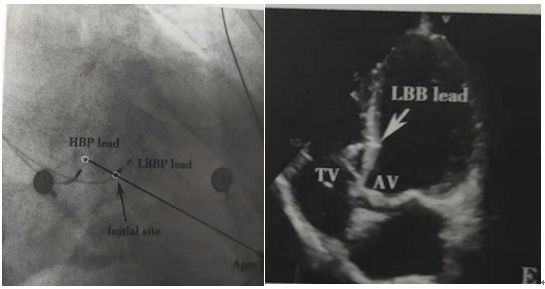

術(shù)中影像

具體手術(shù)過程為:導(dǎo)線標測HIS,影像定位后,將3830導(dǎo)線定位于右室間隔面接近左束支區(qū)域,起搏標測定位后深擰導(dǎo)線至左室間隔內(nèi)膜下,起搏圖形呈右束支傳導(dǎo)延遲形態(tài),術(shù)后常規(guī)心臟超聲示起搏電極位置及深度可且起搏器工作良好。

下圖為標準左束支區(qū)域的影像圖和植入術(shù)后的超聲: